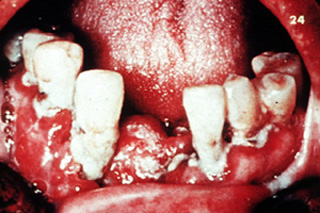

Similitud con enfermedad periodontal

Este paciente presenta una enfermedad

periodontal severa y marcada hiperplasia gingival. Desgraciadamente, el carcinoma

espinocelular imita a menudo la enfermedad periodontal o la gingivitis; uno debe estar en guardia

para descubrir esta ocurrencia. (Photograph courtesy of Dr. S. Rovin.)